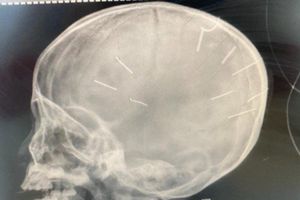

Old  Default Bé gái bị đinh găm trong đầu chưa được phẫu thuật

Thông tin cho rằng sức khỏe của bé đã tiến triển và chuẩn bị được phẫu thuật là không chính xác.

Chiều 26/1, đại diện Bệnh viện Đa khoa Xanh Pôn (Hà Nội), cho biết đến nay, bé Đ.N.A. (3 tuổi, ở Thạch Thất, Hà Nội) vẫn được điều trị tích cực tại khoa Hồi sức cấp cứu Nhi của cơ sở y tế này.

Đại diện này cũng khẳng định thông tin các y bác sĩ đang chuẩn bị phẫu thuật cho bệnh nhi là không chính xác.

Trước đó, chiều 17/1, Bệnh viện Đa khoa Thạch Thất (Hà Nội) tiếp nhận bệnh nhi này trong tình trạng hôn mê, co giật toàn thân. Thời điểm này, bé A. được chẩn đoán viêm màng não và chuyển lên Bệnh viện Đa khoa Xanh Pôn để cấp cứu, điều trị.Tại đây, bé được chụp X-quang và phát hiện có 9 dị vật trong hộp sọ, hình dạng giống đinh ghim.

Bác sĩ Trần Liên Hương, Phó giám đốc Bệnh viện Đa khoa Xanh Pôn, nhận định khó nói trước về tình trạng sức khỏe của bé trong thời gian tới sẽ diễn biến như thế nào. Bà cũng cho biết đây là khoa bệnh nặng, thông thường bệnh nhân khó thể bình phục trong thời gian ngắn. Do đó, với bệnh nhi này, các bác sĩ cần tiếp tục theo dõi sát tình trạng sức khỏe.